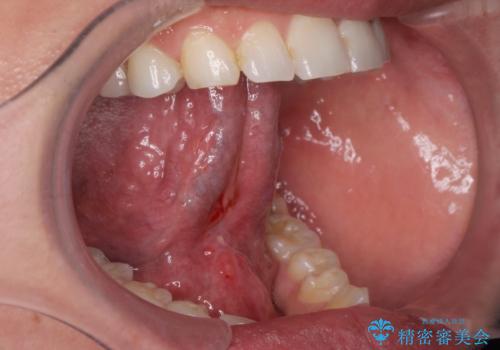

- 滑舌が悪く舌小帯を切りたいとの事で来院。

舌小帯切除術を行いまいした。

舌小帯を切除するだけでは滑舌はよくなりません。

舌の可動域は広がるので滑舌の練習をする必要があります。